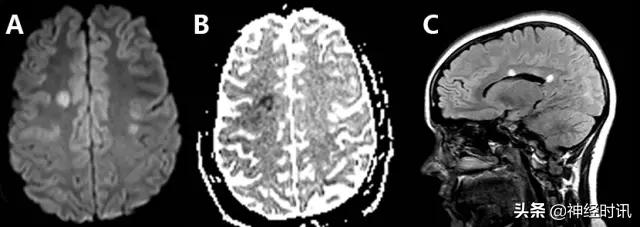

MRI表现包括脑室周围白质,尤其是放射冠和半卵圆中心部位出现一过性的弥散受限和/或T2高信号病变(图19)。甲氨蝶呤所致亚急性脑病发生弥散受限的机制可能与其兴奋性毒性损伤相关,而不是其脱髓鞘作用所致。

图19 一例26岁的女性ALL患者,因鞘内注射甲氨蝶呤治疗10天后出现右上肢无力和一过性言语不清而就诊。MRI显示其左侧中央前回存在弥散受限的圆形病灶(A:DWI,B:ADC),但没有明显的T2异常(C:FLAIR)。几天后的随访MRI(图像未给出)显示弥散受限完全消失,因此最可能为亚急性型甲氨蝶呤毒性反应。